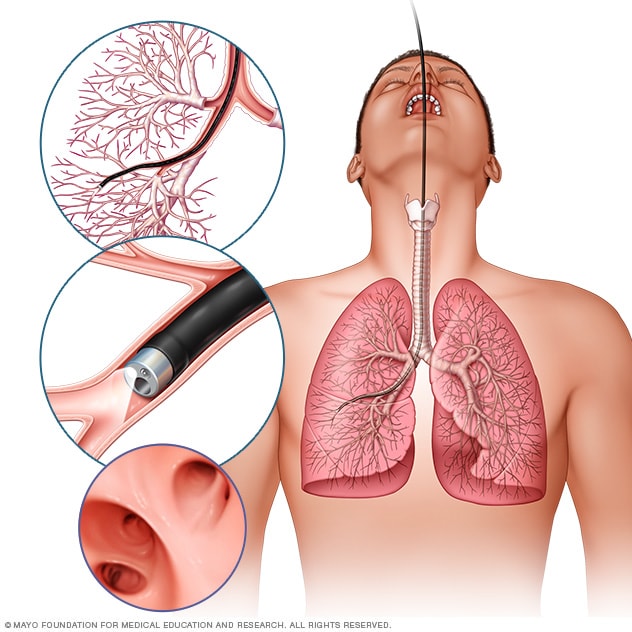

Broncoscopia

En la broncoscopía flexible, el proveedor de atención médica inserta un tubo delgado y flexible a través de la boca o la nariz hasta los pulmones. Una luz y una pequeña cámara en el broncoscopio permiten que el proveedor de atención médica mire dentro de las vías respiratorias de los pulmones.

En la biopsia de pulmón, el proveedor de atención médica extrae muestras de tejido del pulmón muy pequeñas para analizarlas y buscar signos de rechazo e infección. Esta prueba puede realizarse durante una broncoscopía, en la cual el proveedor de atención médica inserta una sonda pequeña y flexible (broncoscopio) en tus pulmones a través de la boca o la nariz. Una luz y una pequeña cámara conectadas al broncoscopio permiten que el proveedor de atención médica mire dentro de las vías respiratorias de los pulmones. El proveedor también puede usar herramientas especiales para extraer muestras pequeñas de tejido pulmonar para analizarlas en un laboratorio.